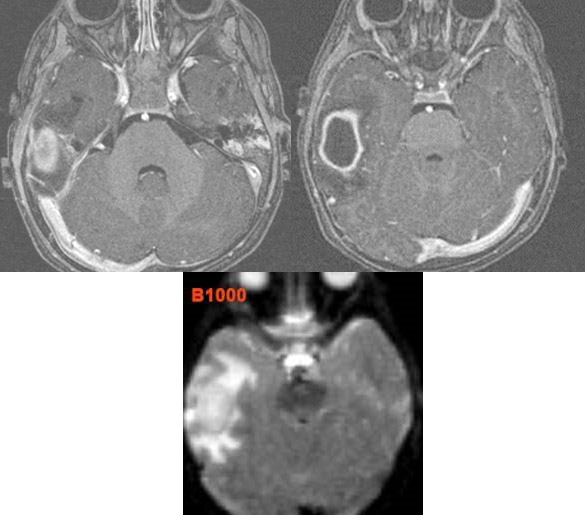

Acute and Subacute Bacterial Otomastoiditis

4. Acute coalescent or otherwise complex otomastoiditis with local complications (indicate specific complications).

5. Acute coalescent or otherwise complex otomastoiditis with intracranial complications (indicate specific complications).